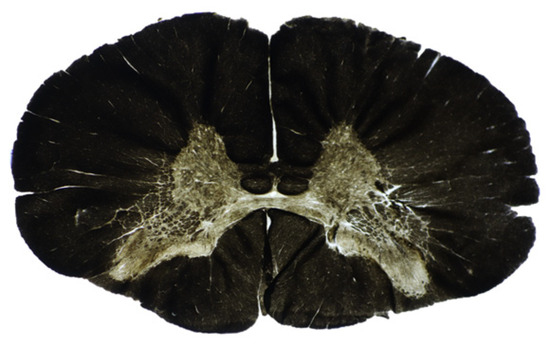

3.2. Histological Data

2.7. Histological Analysis